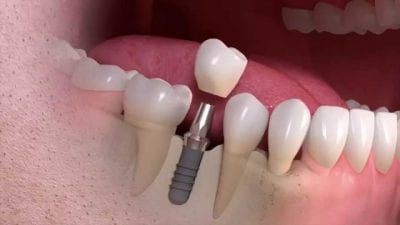

Zubni implanti funkcionišu tako što se titanijumski šraf postavlja u vilicu kao veštački koren zuba, na koji se kasnije postavlja krunica, most ili proteza, čime se trajno nadoknađuju izgubljeni zubi; procedura se obično izvodi u nekoliko faza tokom nekoliko meseci, uključujući vreme za srastanje implanta sa kosti, kako bi se obezbedila dugotrajna stabilnost i funkcija.

Implant je najmodernije i dugotrajno rešenje za nadoknadu izgubljenog zuba. Ne zahteva brušenje susednih zdravih zuba, čuva kost vilice i pruža prirodan izgled i stabilnu funkciju osmeha. U većini slučajeva, implant je dugoročno bolja opcija, ali u situacijama kada nije moguće ugraditi implant zbog nedostatka kosti, opšteg zdravlja ili finansijskih razloga, most može biti praktično i efikasno rešenje.